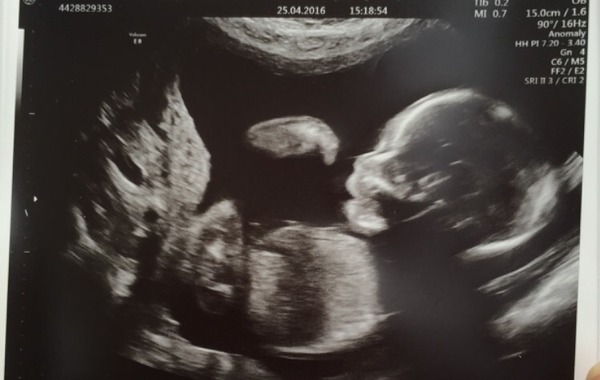

Danni89 · 25/04/2016 17:26

Hi girls, my scan went well- measurements all seem ok Smile

We are team Blue!! Excited! We can now start buying!

Lilliana · 25/04/2016 19:05

Congratulations Danni your picture is much better than ours - we have a lovely shot of baby's back Grin He didn't charge us though as he said he couldn't for that!

Danni89 · 25/04/2016 19:31

Our baby was upside down too.. Had to do a lot of wiggling to get the right measurements lol...

Gorgeous pic danni :) can't wait for my scan in 2 weeks!!